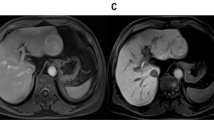

DCE-MRI findings

The RE-time curves of nodules were divided into four types: continuous slow rising, slow rise and fall, rapid rise but slow fall, and rapid rise and fall (Table 2 and Supplementary Fig. 1). The RE-time curve for RN rose slowly in 53.3 % (24/45) of the cases, and rose and fell slowly in 26.7 % (12/45). The RE-time curve for DN rose slowly in 44.3 % (27/61) of the cases, and rose rapidly, but fell slowly in 41.0 % (25/61). The RE-time curve of HCC rose rapidly, but fell slowly in 40.5 % (15/37) of the cases, and rose and fell rapidly in 29.7 % (11/37). All of the DCE-MRI parameters increased along with increasing grade of nodule malignancy (Table 3 and Fig. 3). The highest Ktrans and iAUC values were seen in HCC, followed by DN and RN (all P < 0.05). Kep was higher in HCC than DN and RN (both P < 0.05), and Ve was higher in HCC than RN (P < 0.05). There was a positive correlation between each parameter of DCE-MRI and the pathological classification of liver nodules (rKtrans = 0.540, rKep = 0.219, rVe = 0.206, riAUC = 0.521, all P < 0.05). In the diagnosis of DN and HCC, Ktrans and iAUC had higher AUROC than that of Kep and Ve with high specificity, but low sensitivity (Table 4 and Fig. 4). For HCC diagnosis, Ktrans and iAUC had higher AUROC than that of Kep and Ve , with both high specificity and high sensitivity (Table 4 and Fig. 4). Ordinal logistic regression analysis showed that Ktrans was a potential predictive variable for the pathological classification of liver nodules (goodness of fit, 0.970; 95 % confidence intervals, 13.751-24.958). In contrast, iAUC had no predictive value for the pathological classification of liver nodules.

Imaging findings of different kinds of nodules. Images of T2WI, Ktrans, relative enhancement-time curve, and haematoxylin-eosin (HE)-stained samples (Original magnification, ×200) of RN, DN, HCC in rats. The images of Ktrans show the selection of ROIs of the nodules (yellow circles). In RE-time curves, the red, green, and yellow curves represent artery input function, vein input function, and the relative enhancement degree of nodule, respectively. The RE-time curve of RN has a constant slow rise, and of DN it rises rapidly, but falls slowly, and the RE-time curve of HCC rises and falls rapidly. HE stain shows that the size and shape of cells in RN are similar to normal liver cells, but its arrangement is random and disorganized. The cells in DN are atypical and with increased cellular density. And the cells in HCC are obviously atypical and necrosis (arrow) is more likely to see